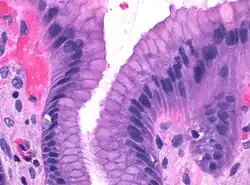

Epiteliální buňky mají cylindrický tvar. Jsou vysoké 20-40 µm. Jádro, kulové či oválné, je uložené u báze buněk, kde se také nachází granulární endoplazmatické retikulum a nad ním Golgiho aparát. V apikální části buněk se vyskytují četná světlá hlenová granula.[5]

Mucinózní buňky krčků, které lemují žaludeční žlázky, jsou jim podobné. Osahují typická kulatá jádra a apikálně uložená sekreční granula, ale jsou nižší a mohou mít nepravidelný tvar.[6][7]